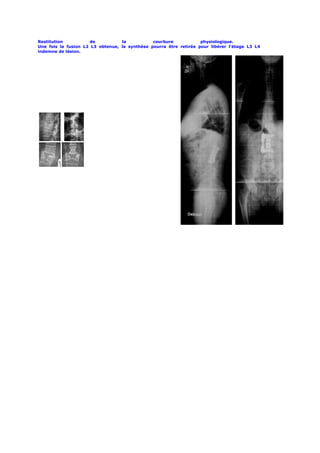

A2 A3.1 A3.3

B1 B2

Fractures étagées de

Fractures étagées de L1

T10 à L2 en rotation

(Type                  B)

(Type             C).

Avec           paraplégie

Traitées

sequellaire.

orthopédiquement.

Cyphose      douloureuse,

Aspect de scoliose

lésion cutanée en regard

secondaire         de

du sommet de la cyphose.

sommet T12.